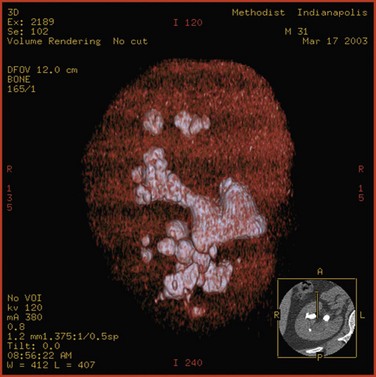

Therefore, at present, the most accurate method to estimate the volume of a staghorn calculus is CT with three-dimensional reconstruction. This technique permits highly accurate determination of stone volume as well as the three linear dimensions of renal calculi and correlates well with the actual volume of the stone, as measured by water displacement (Lam et al, 1992c). Thiruchelvam and coworkers (2005) reported that an added benefit of three-dimensional image reconstruction is in planning for subsequent percutaneous stone removal. However, three-dimensional CT reconstructions are costly, time consuming, and not widely available, thus limiting the utility of this technology. Nadler and associates (2004) have reported the use of coronal reconstructions of axial CT images to calculate the craniocaudal length of stones, which can facilitate more economical stone volume calculations.

Although CT attenuation values can distinguish some stone types in vivo, such as uric acid from calcium stones, the use of attenuation values alone results in considerable overlap; the range of values for calcium oxalate monohydrate and struvite stones does not allow these types to be confidently distinguished. Furthermore, it is not certain that the ease with which a stone is fragmented by SWL can be predicted by knowing only the major mineral composition of the stone. For example, cystine stones, which are considered difficult to break, have been shown in certain cases to break easily (Bhatta et al, 1989). Williams and associates (2003), too, reported that the variability in stone fragility to shockwaves is large, even within groups defined by mineral composition. It is likely that this variability in fragility could be due to variation in stone composition or structure, including variable amounts of secondary mineral in the stone, variation in the spatial arrangement of the secondary mineral within the stone, and variation in the layer structures of the primary and secondary minerals within a stone. Williams and associates (2002) also reported that displaying the data acquired by helical CT with use of bone windows can reveal remarkable internal structural detail of kidney calculi (Fig. 48–4 on the Expert Consult website

). It is clear that CT provides a wealth of information about stone characteristics. However, additional work is needed to determine the utility of this powerful imaging tool in determining the susceptibility of a given stone to SWL.

Figure 48–4 Photographic and helical CT images show structural variability in stones of the same type. Note that although all stones depicted are calcium oxalate in type, some have a mottled structure and others have a lamellar structure.